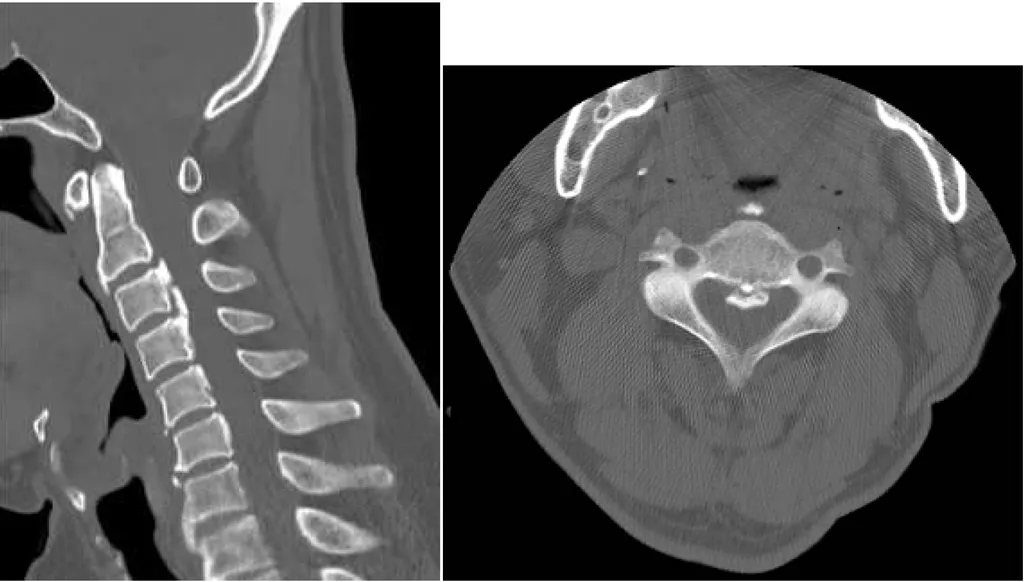

60 歲男性病患因長期頸部疼痛接受電腦斷層檢查,發現第歲男性病患因長期頸部疼痛接受電腦斷層檢查 3 至第 4 頸椎有一鈣化病灶如圖。其診斷為何?

這張電腦斷層影像的關鍵在於頸椎椎體後方、脊髓前方出現的連續性高密度鈣化病灶,這正是後縱韌帶骨化症的典型表現。

-A:錯在舊性椎體骨折通常會看到骨折線癒合或骨贅增生,但不會是這種沿著韌帶分佈的連續性鈣化。